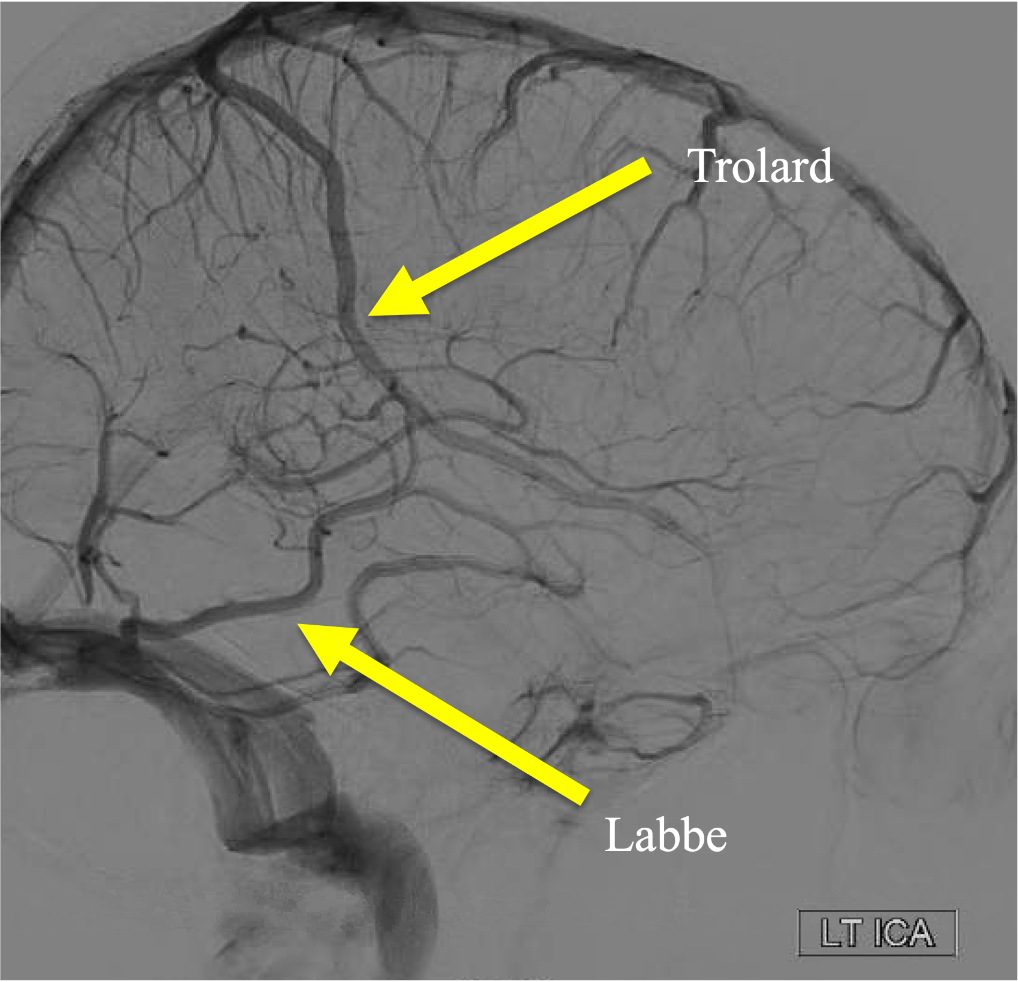

On the venous phase of this lateral L ICA injection, name the superficial vein: